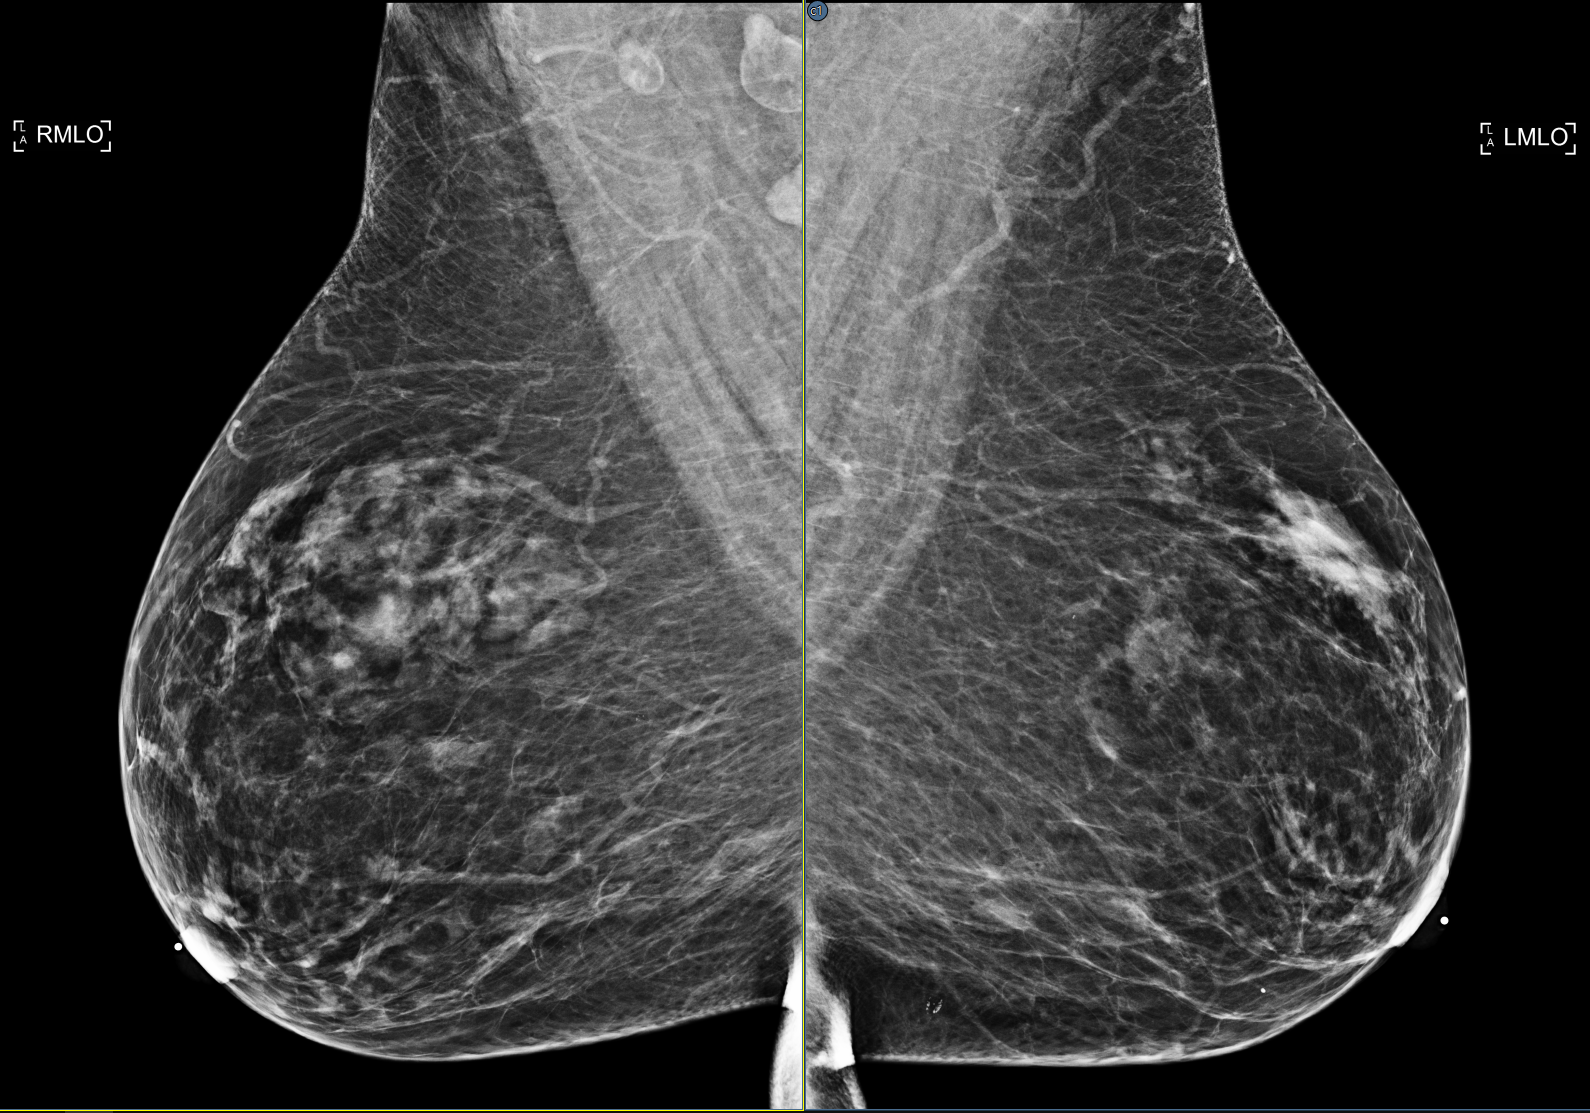

A location reference in DeepHealth’s mammo CAD objects could result in incorrect cross references. DeepHealth resolved the problem using version tags. The viewer recognizes these tags so it can correct the result in existing CAD objects and apply the correct indices for new CAD objects.

The viewer supports the DeepHealth Saige-Density SR objects, displaying the case density score in the CAD header and, optionally, in the overlay data using the Breast Composition info tag.

Additional information from iCAD SR objects is displayed, including the case score and case score label in the CAD header. If synthetic 2D images and BTO series are present in the same study, cross correlation is enabled allowing the user to jump to the tomo slice corresponding to the location selected. Lastly, the graphic icons used to represent iCAD calcification clusters (rotated square) and masses (ellipse) have been updated.

DeepHealth CAD suspicion levels are indicated in the finding icon in the stack ruler. One to three lines indicate low, medium and high suspicion levels, respectively. No line indicates no suspicion level defined in the CAD object. Additionally, if the CAD object defines a color for the finding markers, the color is applied to the graphics in the image and stack ruler. This feature can be disabled from the Use color for CAD markers setting on the Options/Presentation States/Mammography CAD SR settings page.

The viewer supports ScreenPoint’s Transpara CAD objects.

The CAD header with the Transpara logo contains the number of calcification and mass findinds, the algorithm version and the Transpara score (integer value between 0 and 10).

Calcifications are marked by a diamond outline and the contour of individual calcifications.

Masses are marked by their contour (plus the default marker if enabled).

There’s an additional type of finding for Screenpoint called “decision support”, which describes a more general region of interest. So far, Transpara is the only CAD that uses this type but this might change in the future. In order to have a more general tool, the viewer refers to this type of finding as “region of interest”.

A new option has been added to both the global and local CAD menu to show/hide regions of interest. The default is off.

In case of Transpara, regions of interest appear as color-coded circles that usually - but not always - have a score associated with them.

Support for DeepHealth Saige-Q SR objects has been added. The triage header displays the algorithm name and version, and the case assessment type and value.

Added support for Hologic's Genius AI™ objects.

Genius AI™ Detection* (* pending FDA clearance) is a software module intended to identify suspicious breast lesions appearing as soft-tissue densities (masses, architectural distortions, and asymmetries) or calcification clusters in Hologic Selenia Dimensions breast tomosynthesis images, using deep learning neural networks.

See Cross_Correlate_2D_CAD_in_Tomosynthesis_Images and CAD_Certainty_Scores

Added support for DeepHealth's updated CAD objects in which findings marked in 2D images are correlated to a position in a specific BTO frame or frames. See Cross_Correlate_2D_CAD_in_Tomosynthesis_Images